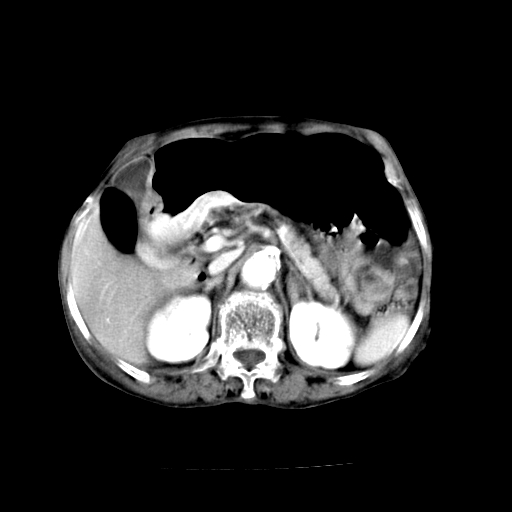

标题: CT19149:女,68岁,腹胀、恶心两周。 [打印本页]

标题: CT19149:女,68岁,腹胀、恶心两周。

女,68岁,腹胀、恶心两周,先做ct平扫,当时家属不同意强化,6天后家属要求增强扫描。

1、胃窦癌; 2、局灶性脂肪肝。

1、胃窦癌?建议行胃镜!; 2、局灶性脂肪肝。

1)胃窦壁厚,考虑胃窦癌?建议行胃镜检查。 2)局灶性脂肪肝。